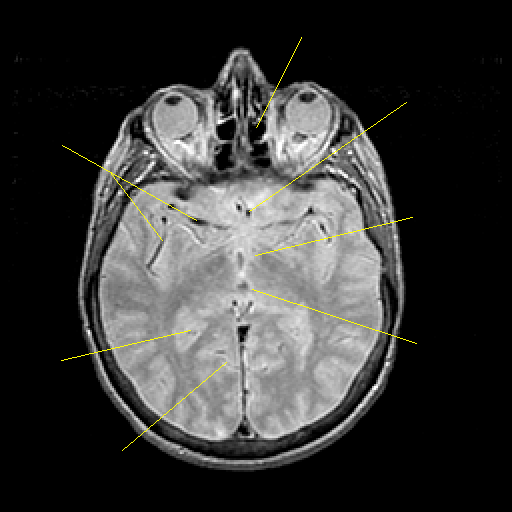

Proton density-weighted structural MR: Slice 25

Pointers

Labeled